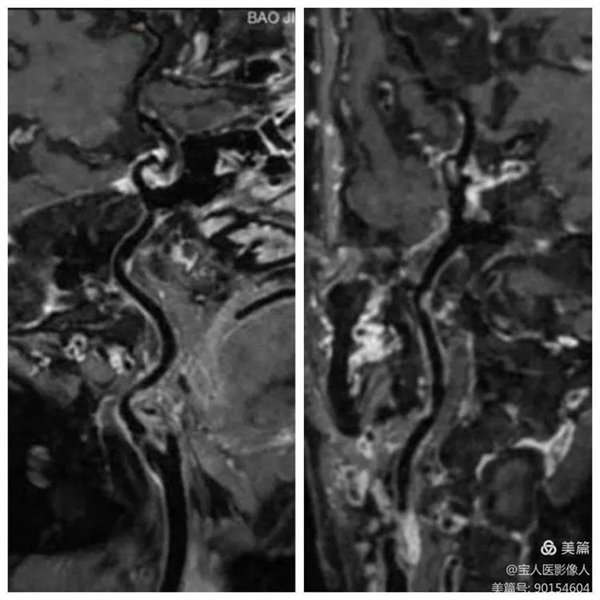

48岁的一名男性患者因长期头痛行颅脑MRI检查,有病变提示,遂进一步行头颈部血管增强磁共振成像(CE-MRA)和血管壁成像(HR-VWI),诊断为颈内动脉颅外段壁间血肿。

CE-MRA完美显示管腔,右侧颈内动脉狭窄

HR-VWI管壁明显增厚,呈高信号

HR-VWI管壁增厚,呈新月形高信号

患者行CE-MRA、HR-VWI检查能清晰显示头颈部血管腔、血管壁及脑实质,完美显示动脉瘤和评估动脉瘤稳定性。